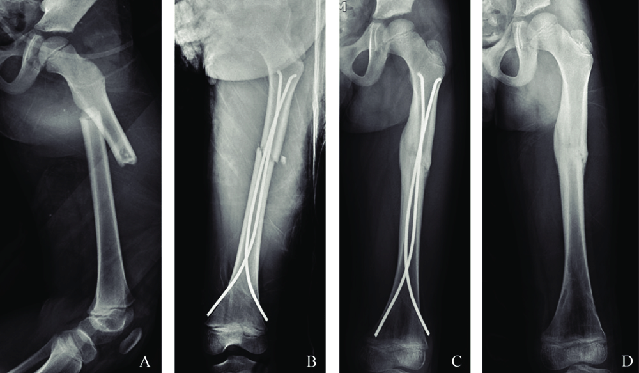

Femur shaft Fracture